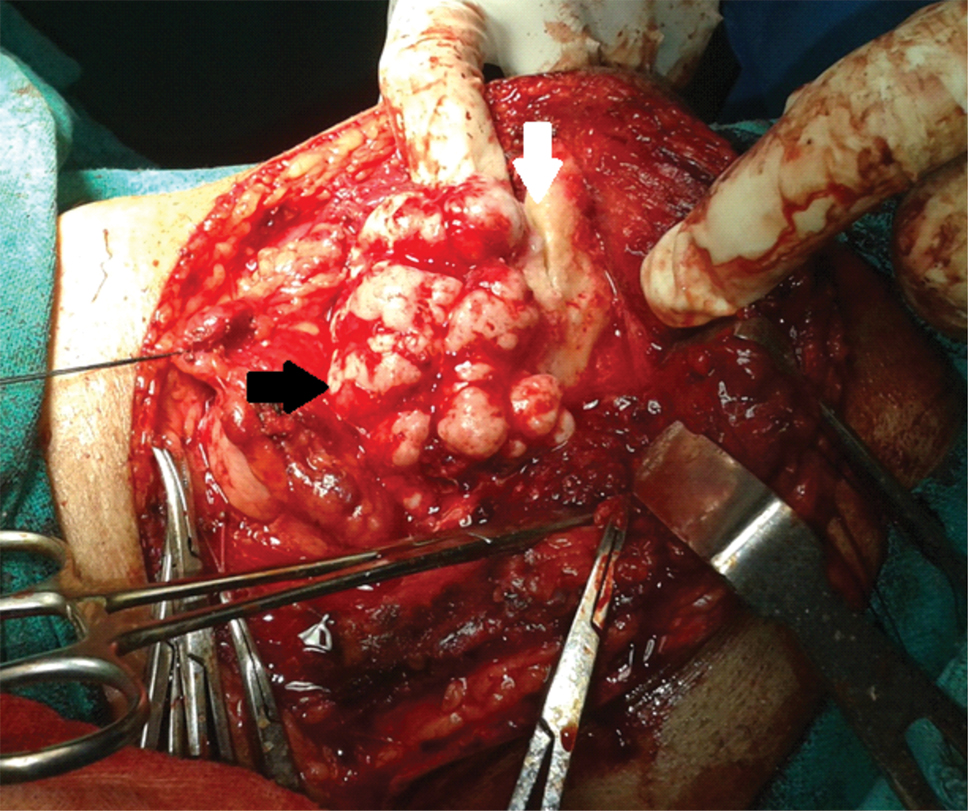

As patient was concerned about such large swelling over his face, plan of excision was made on the basis of cosmetic grounds. Patient was planned for excision with transcervical approach under general anaesthesia. A curvilinear incision was made from the chin midline, extending over the swelling, well below to preserve the marginal mandibular nerve and reaching till the mastoid tip. Subplatysmal flaps were elevated. A lobulated bony lesion was seen over the lower border of left mandible involving the buccal aspect extending medially to involve lingual aspect also [Table/Fig-3]. This bony tumour was cut from the mandible taking wide margin using oscillating saw with preservation of inferior alveolar nerve, alveolar rim and dentition. The mandible was reinforced using titanium plates [Table/Fig-4]. Histopathological examination showed mature lamellar bone consistent with compact osteoma [Table/Fig-5]. Patient did well in post-operative period.

Intraoperative image showing lobulated hard bony tumour involving lower border, both lingual and buccal surface, extending up to the angle of mandible (white arrow- mandible, black arrow- osteoma).